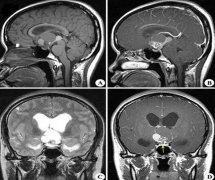

颅咽管瘤专家如何?颅咽管瘤是儿童时期常见的累及下丘脑-垂体区的良性组织肿瘤,在成人中比较少见。囊性颅咽管瘤占肿瘤的90%以上。囊性颅咽管瘤的较佳治疗方法仍有争议...

Q:我家孩子10岁,刚查出得了颅咽管瘤,这种颅咽管瘤能活多久?怎么治疗比较好?后期能回归正常生活吗? A:颅咽管瘤能活多久? 首先需要来了解下什么是颅咽管瘤。颅咽管瘤是由...

颅咽管瘤 有不复发的吗?颅咽管瘤是一种生长缓慢的良性脑瘤,发生在脑下垂体(脑下垂体是位于大脑底部的一个小的内分泌腺,它产生几种重要的激素)和下丘脑(一个控制脑下垂体释放...